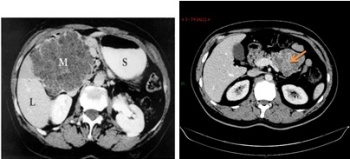

1. טומוגרפיה ממוחשבת - בדיקת הבחירה לאבחון שאתות בלבלב. בעזרתה מודגמות כיום השאת ומידת התפשטותה באחורי הצפק (רטרופריטונאום), כולל חדירה לכלי הדם הגדולים. דיוק האבחנה בטומוגרפיה ממוחשבת הוא גבוה, בלא קשר למיקום השאת (תצלום 19.9).

לעתים ייראו כיס מרה גדול על-שם קורבזיה (תצלום 20.9) והרחבה של דרכי המרה החוץ והתוך-כבדיות (תצלום 21.9).